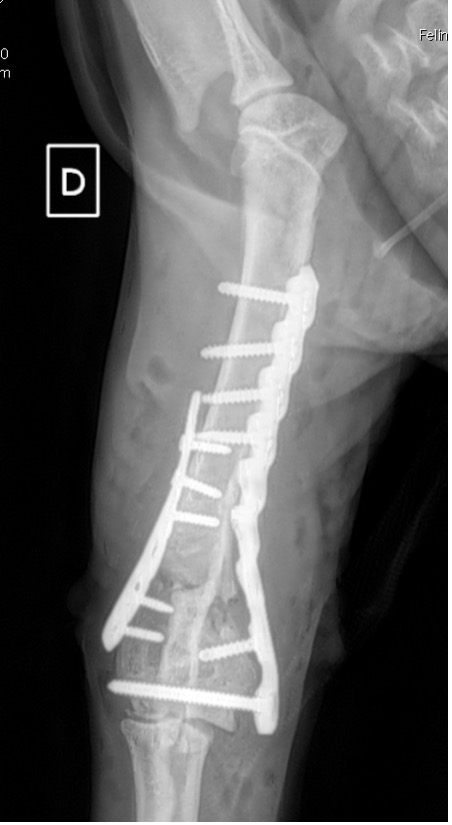

L’avènement récent des plaques anatomiques constitue une nouvelle option dans le traitement de ces fractures : dans l’exemple 3 (chat Ragdoll), une plaque anatomique médiale de 2 mm acceptant des vis de 1,6 et 2 mm a été utilisée seule avec succès.

Exemple 3 :

Figure 11 : Post-Op Immédiat

Figure 12 : Post-Op 1 mois